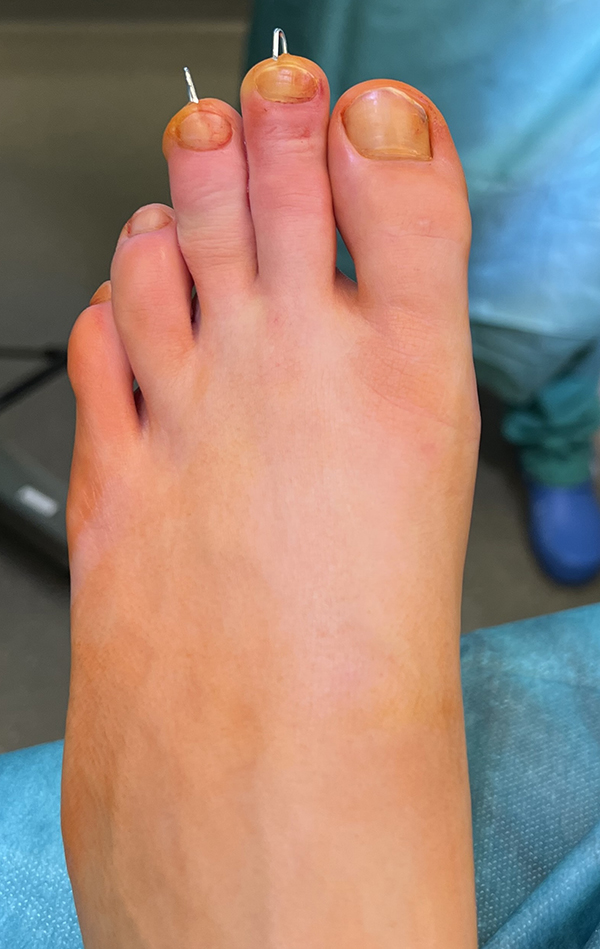

Zehenfehlstellungen

Im Rahmen von sub- oder superduktischen Zehen oder bei Vorhandensein einer Kirner-Deformität werden in unserem Team Kleinzehenkorrekturen entweder komplett oder inkomplett und sowohl am Grundglied kombiniert als auch am Mittelglied durchgeführt (Abb. 20).

Abb. 20 a-d: Krallenzehen mit subluxierter Gelenkstellung. Präoperatives Röntgenbild d. p. (a), intraoperative Nadelmarkierung für die entsprechenden Osteotomien (b); postoperatives Röntgenbild mit einer Multilevel-Korrektur der Zehen (c) und klinischer postoperativer Verlauf (d). In der letzten Aufnahme zeigt sich gut die bereits korrigierte Zehenstellung am rechten und die noch nicht versorgten Zehen am linken Fuß.

Zum Lesen der Bildbeschreibung und zur Vollansicht bitte die Bilder anklicken. Bilder: A. Helmers.